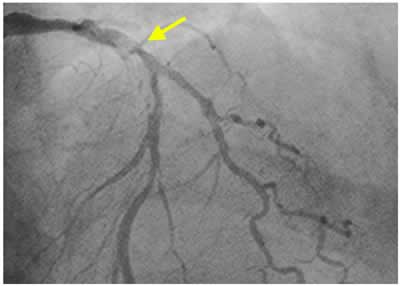

| Diagnosis: AP, SVD Present Illness: '98.11.2 RA+stenting for #1 '01.6.14 RA+stenting for #1-2 '01.9.26 RA for #11 |

| Final CAG Findings:'01.9.18 LVG: no asynergy, EF: 68% CAG: #5 50%, #6 9 |